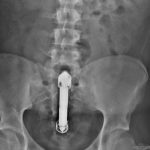

Vibrátort műtöttek ki a fenekéből: Az interneten még azt is élőben követhető, ahogy egy férfi fenekéből eltávolítanak egy vibrátort. Egy Grawly nevű twitterező legalábbis az elejétől a végéig publikálta az eseményt.

Élőben közvetítette a Twitteren egy férfi, ahogy eltávolítanak egy óriási vibrátort a végbeléből – írja a DailyDot. A Grawly néven twittelő fiatalember – oldala még mindig elérhető, itt – múlt csütörtökön ment el orvoshoz, hogy szedjék ki belőle a nagy dildót, amelyet ráadásul nem tudott kikapcsolni, úgyhogy a Twitteren azon is bosszankodott, hogy az Energizer miért gyárt ilyen tartós elemet. Jó, az orvoshoz ment kifejezés nem teljesen áll: az apját ébresztette fel az éjszaka közepén, hogy vigye már be az ügyeletre. Bevitte.

– Belenéztem a sürgősségis ápolónő szemébe, és így szóltam, nem cifrázom, egy vibrátor van a fenekemben – jelentkezett be a kórházból… A teljes cikk itt.